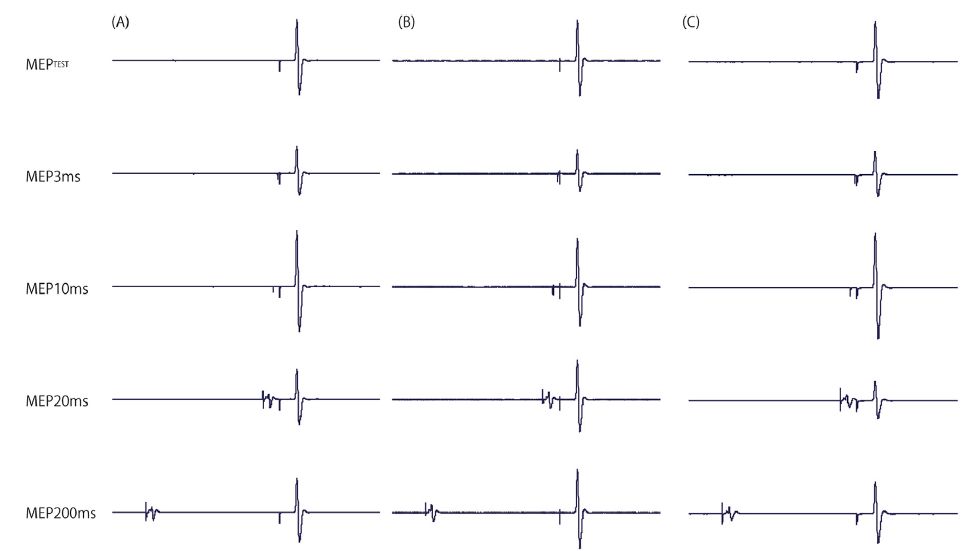

Sato D, Yamashiro K, Yoshida T, Onishi H, Shimoyama Y, Maruyama A: Effects of water immersion on short- and long-latency afferent inhibition, short-interval intracortical inhibition, and intracortical facilitation. Clinical Neurophysiology. 124:1846-1852, 2013.